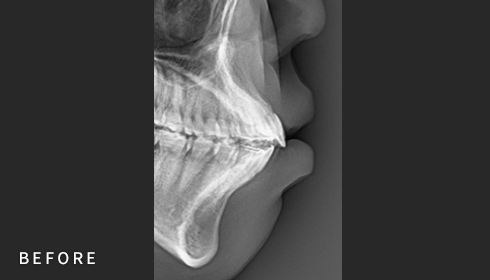

• Cephalometric X-ray 촬영

2~3초의 짧은 시간 안에

얼굴의 측면 엑스레이 촬영이 가능합니다.